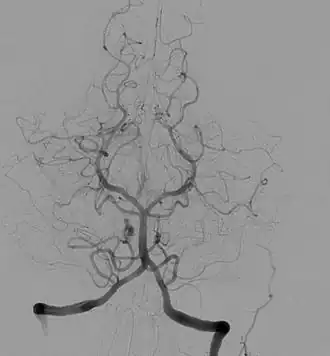

- Ангиография головного мозга, в поперечной проекции. Вертобро-базилярный, задней мозговой артерии бассейны.